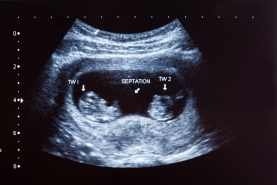

Echografieën

Een echografie geeft heel wat informatie over het verloop van de zwangerschap. Ultrasone (niet-hoorbare) geluidsgolven weerkaatsen op de inwendige organen. Het terugkerende geluid (echo) wordt opgevangen en omgevormd tot een beeld. Zo wordt de baby, de moederkoek ... in beeld gebracht.

Een normale echografie is geen garantie dat alles vlekkeloos zal verlopen. De positie van je baby tijdens het onderzoek, de hoeveelheid vruchtwater en de lichaamsbouw van de mama zijn factoren die het onderzoek kunnen bemoeilijken. Niet alle afwijkingen kunnen worden opgespoord: sommige aandoeningen zijn niet echografisch aantoonbaar of zijn niet zichtbaar.

Er worden 2 echografieën aanbevolen, één in het eerste en één in het tweede trimester van de zwangerschap. Een derde echografie in het derde trimester kan worden overwogen. Voor 3 echografieën is er een tegemoetkoming van het ziekenfonds voorzien. Elke echografie heeft een specifiek doel.

Zwangerschapsduur: tussen 11 en 14 weken

• De kruin-romplengte van je baby wordt gemeten om de zwangerschapsduur en de vermoedelijke bevallingsdatum te bepalen.

• Er wordt nagegaan of het eventueel om een meerlingzwangerschap gaat.

• Het risico op chromosomale afwijkingen wordt bepaald. Door de nekplooi van je baby te meten kan een verhoogd risico op onder andere het syndroom van Down worden opgespoord.